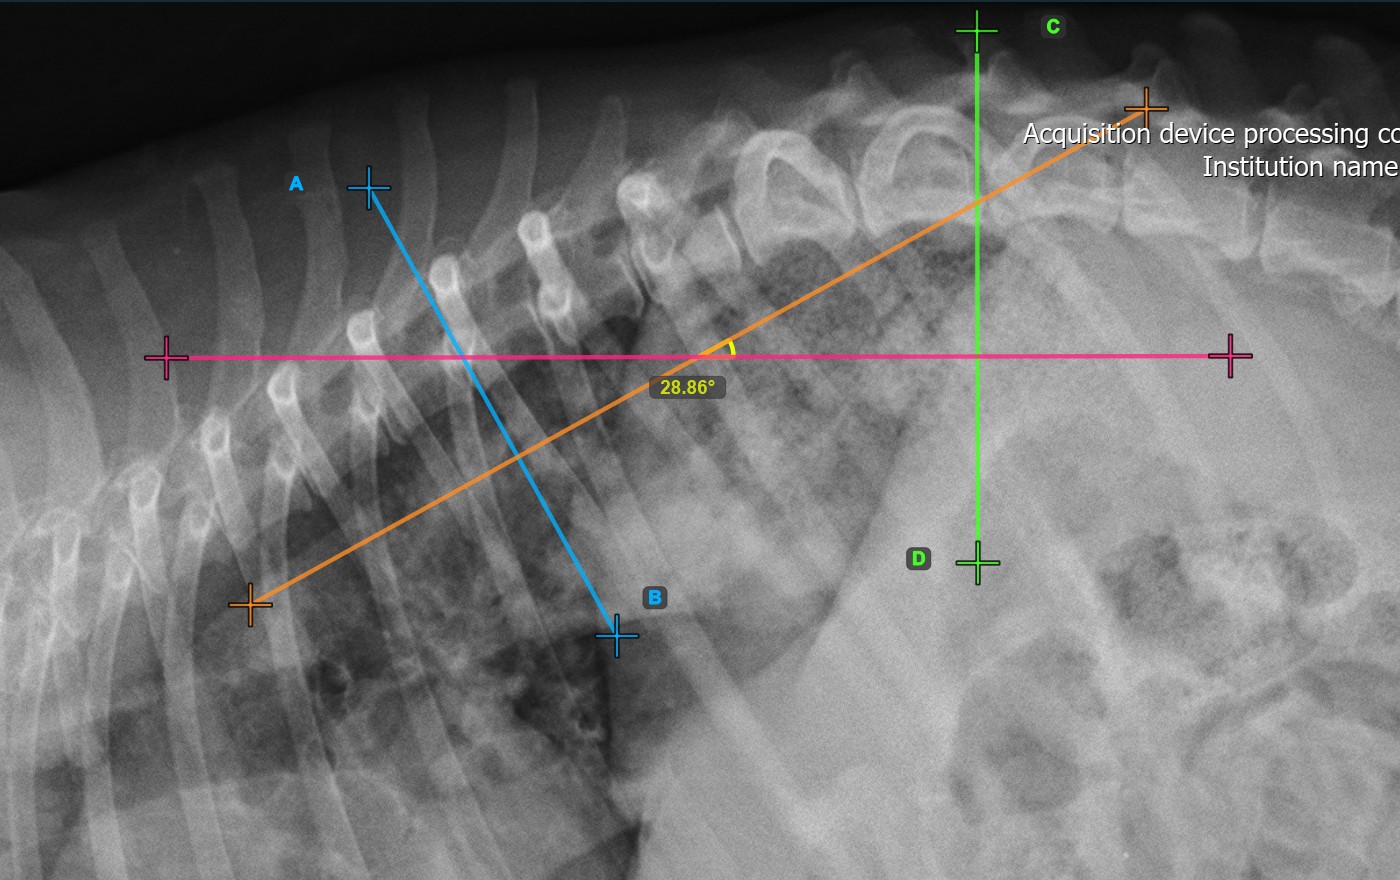

The Cobb Angle measurement is used to quantify the deformity of the spine and the angle of deviation in patients, typically for conditions like scoliosis. Select the Cobb Angle measurement from the Advanced Measurement menu and assign the left mouse button to it.

Start the measurement by marking the first vertebral line on the spine.

Identify the vertebral endplate at the initial point of the largest spinal curve deformity. Place the start and end point of the first vertebral line precisely along the identified endplate. Adjust each point on the scene to better align the line with the endplate if needed.

The image below represents a typical placement of the first vertebral line.

Mark the second vertebral line on the spine to calculate the deformity.

Identify the vertebral endplate at the opposite end of the largest spinal curve deformity. Place the start and end point of the second vertebral line precisely along the identified endplate. Adjust each point on the scene to better align the line with the endplate if needed.

The Cobb Angle measurement will be automatically calculated and completed once the two vertebral lines are placed, indicating the angle of spinal curviture in degrees.

The image below represents a typical placement of the second vertebral line.

Modify the position and orientation of the two vertebral lines to automatically recalculate the Cobb Angle.